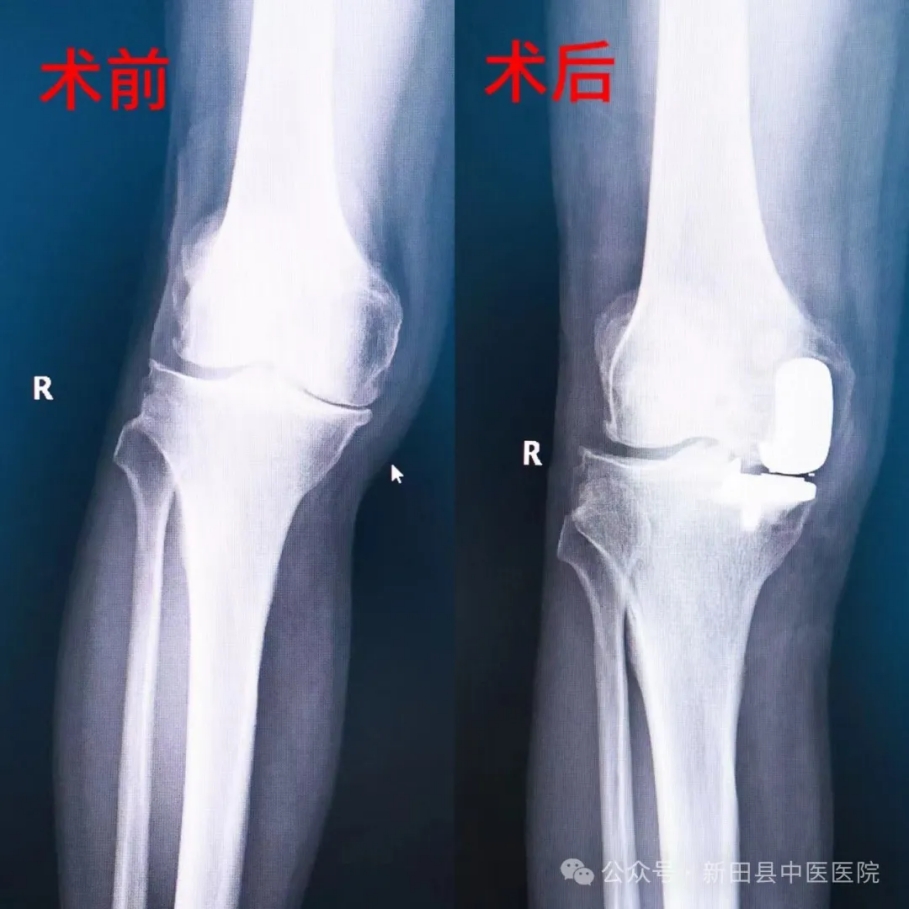

患者朱大爷,现年77岁,因右膝关节疼痛数月,加重伴行走困难一周来我院骨伤科门诊就诊,经全面仔细体查并结合影像检查资料,诊断为“右膝关节骨性关节炎”收住骨伤二科治疗。考虑患者为膝关节内侧单间室病变,外侧间室及髌股关节正常,治疗方案拟行右侧膝关节单髁置换术。经积极完善相关术前检查并与患者及家属充分沟通取得同意后,8月12日,科主任谭继勇带领科室医疗团队精心为朱大爷行了右侧膝关节单髁置换术。手术顺利,术中出血量少,创伤小,术后患者恢复良好。

术前术后患者膝关节影像对比